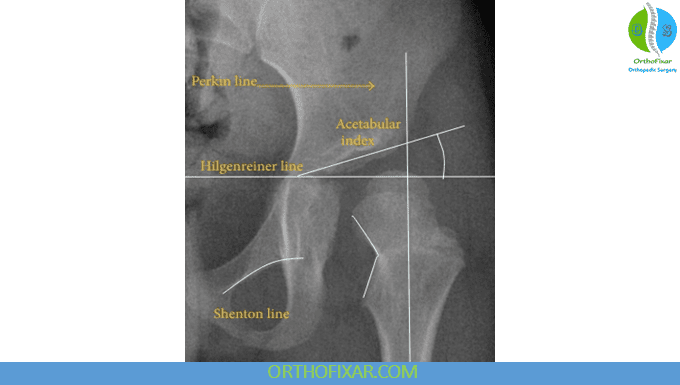

13. Acetabular index (Hilgenreiner angle / Sharp angle)

Assess acetabular development, especially in pediatric patients.

- Normal values: < 30° in newborns, < 20° by age 2, and < 36° in adults.

Higher angles indicate acetabular dysplasia, and the steeper the roof, the less stable the femoral head.

16. Shenton’s line

This smooth arc follows the medial femoral neck and inferior pubic ramus. A broken Shenton’s line suggests femoral neck fracture, dislocation, or SCFE.

22. Hilgenreiner’s and Perkins’ lines (pediatric dysplasia evaluation)

- Hilgenreiner’s line: horizontal line through the inferomedial ilium.

- Perkins’ line: vertical line through the superolateral acetabular edge.

In normal development, the femoral head ossification center lies in the inferomedial quadrant.

If the ossification center is in the superolateral quadrant, the finding suggests dislocation or DDH. In newborns, the ossification center may not yet be visible.